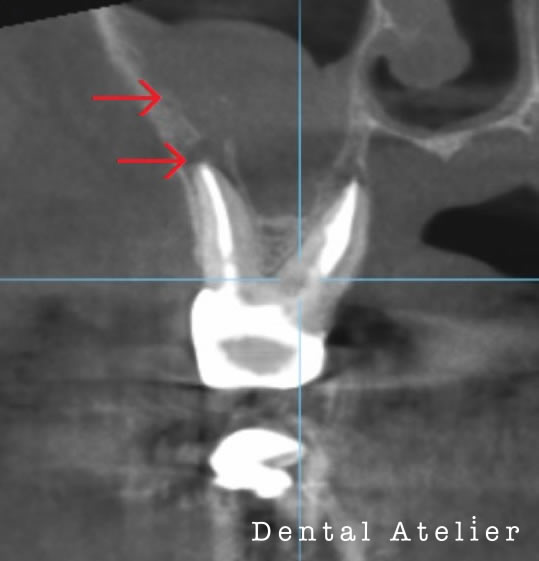

若い頃に神経を取る治療をしたが、10年前に膿が溜まって歯ぐきが腫れてきたので、根管の再治療を行うも、現在まで違和感が消えないと当院を来院しました。

階段を降りる時に響くかんじ、アルコールを飲むと違和感がでるとの事でした。

初診時

根の先端から、副鼻腔(蓄膿症になる鼻の空洞)へ感染が起り、矢印の場所が灰色になっています。膿が溜まっています。

根管治療、一か月後

無菌的な処置により、炎症が引いて、矢印の場所に正常な黒い空洞に戻ってきました。歯が原因で鼻の空洞に炎症が起ることがあります。歯性上顎洞炎。